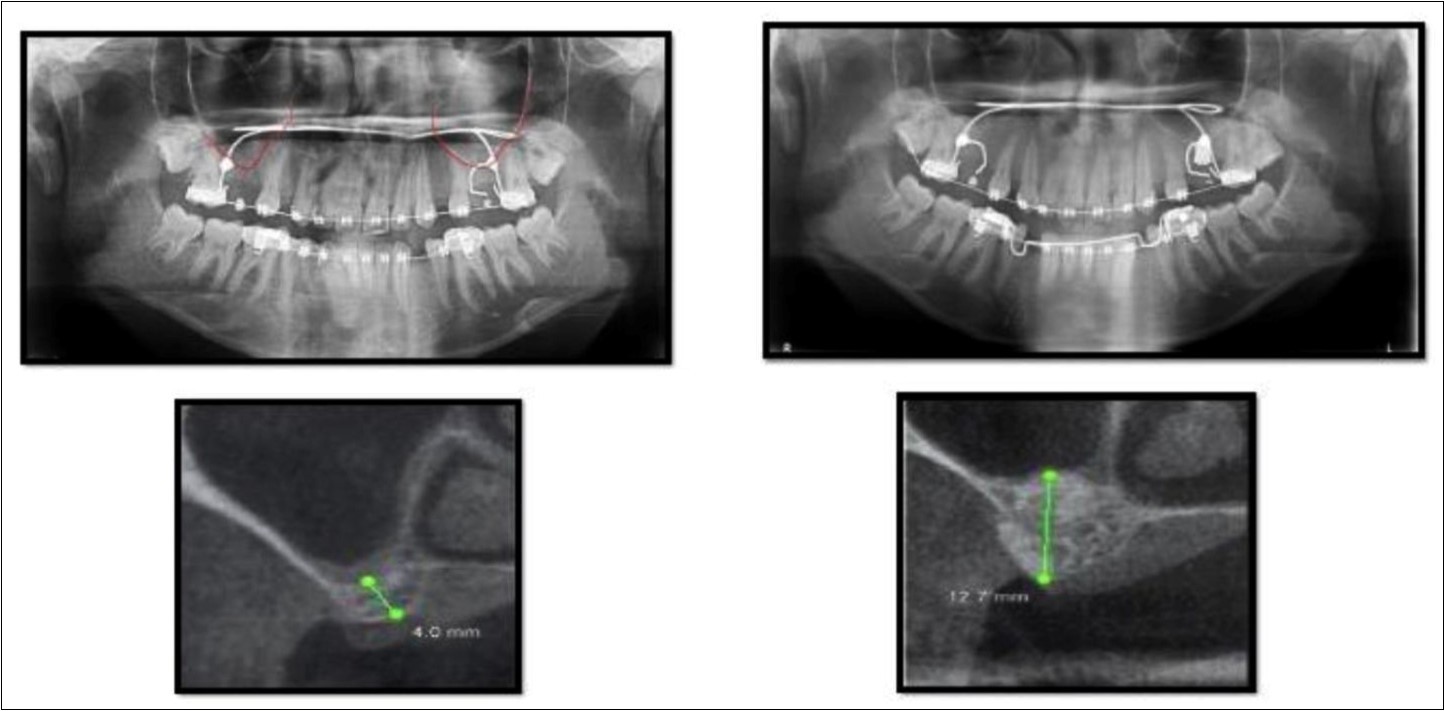

Case Report 4

A 19 year old young woman was referred to Department seeking options for rehabilitation of missing right upper first molar with fixed prosthesis as she was uncomfortable with the removable partial denture in relation to 16. The residual bone height in region was 4 mm in 16 tooth region. Patient was taken-up for direct sinus elevation via lateral window approach for sinus augmentation in relation to 16. Under aseptic conditions and local anesthesia, lateral wall of maxilla was exposed after muco-periosteal flap elevation. A window was created of 1cm diameter corresponding to apical aspect of 16. Sinus membrane was identified and elevated using sinus elevators and reamers without perforating the lining. Once the sinus membrane was elevated, graft material was dispensed to achieve an augmentation of 1cm assessed clinically and confirmed using post-operative OPG. At the end of 6 months, a CBCT scan showed an increased bone height of 12.7 mm. (Figure 6)

Figure 6.Pre-operative and post-operative Orthopantomographs and cross sections of CBCT showing residual alveolar bone height